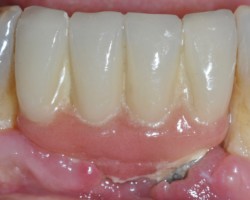

Avant-Après :

Maintenance péri-implantaire

Détartrage des prothèses avec les inserts PerioSoft

Polissage des surfaces avec la buse perio maintenance et poudre perio AIR-N-GO easy

Débridement des spires avec les inserts ImplantProtect et polissage ciblé avec la buse perio et poudre perio AIR-N-GO easy

- Prévention et traitement de la mucosite

- Traitement chirurgical de la péri-implantite

- Maintenance